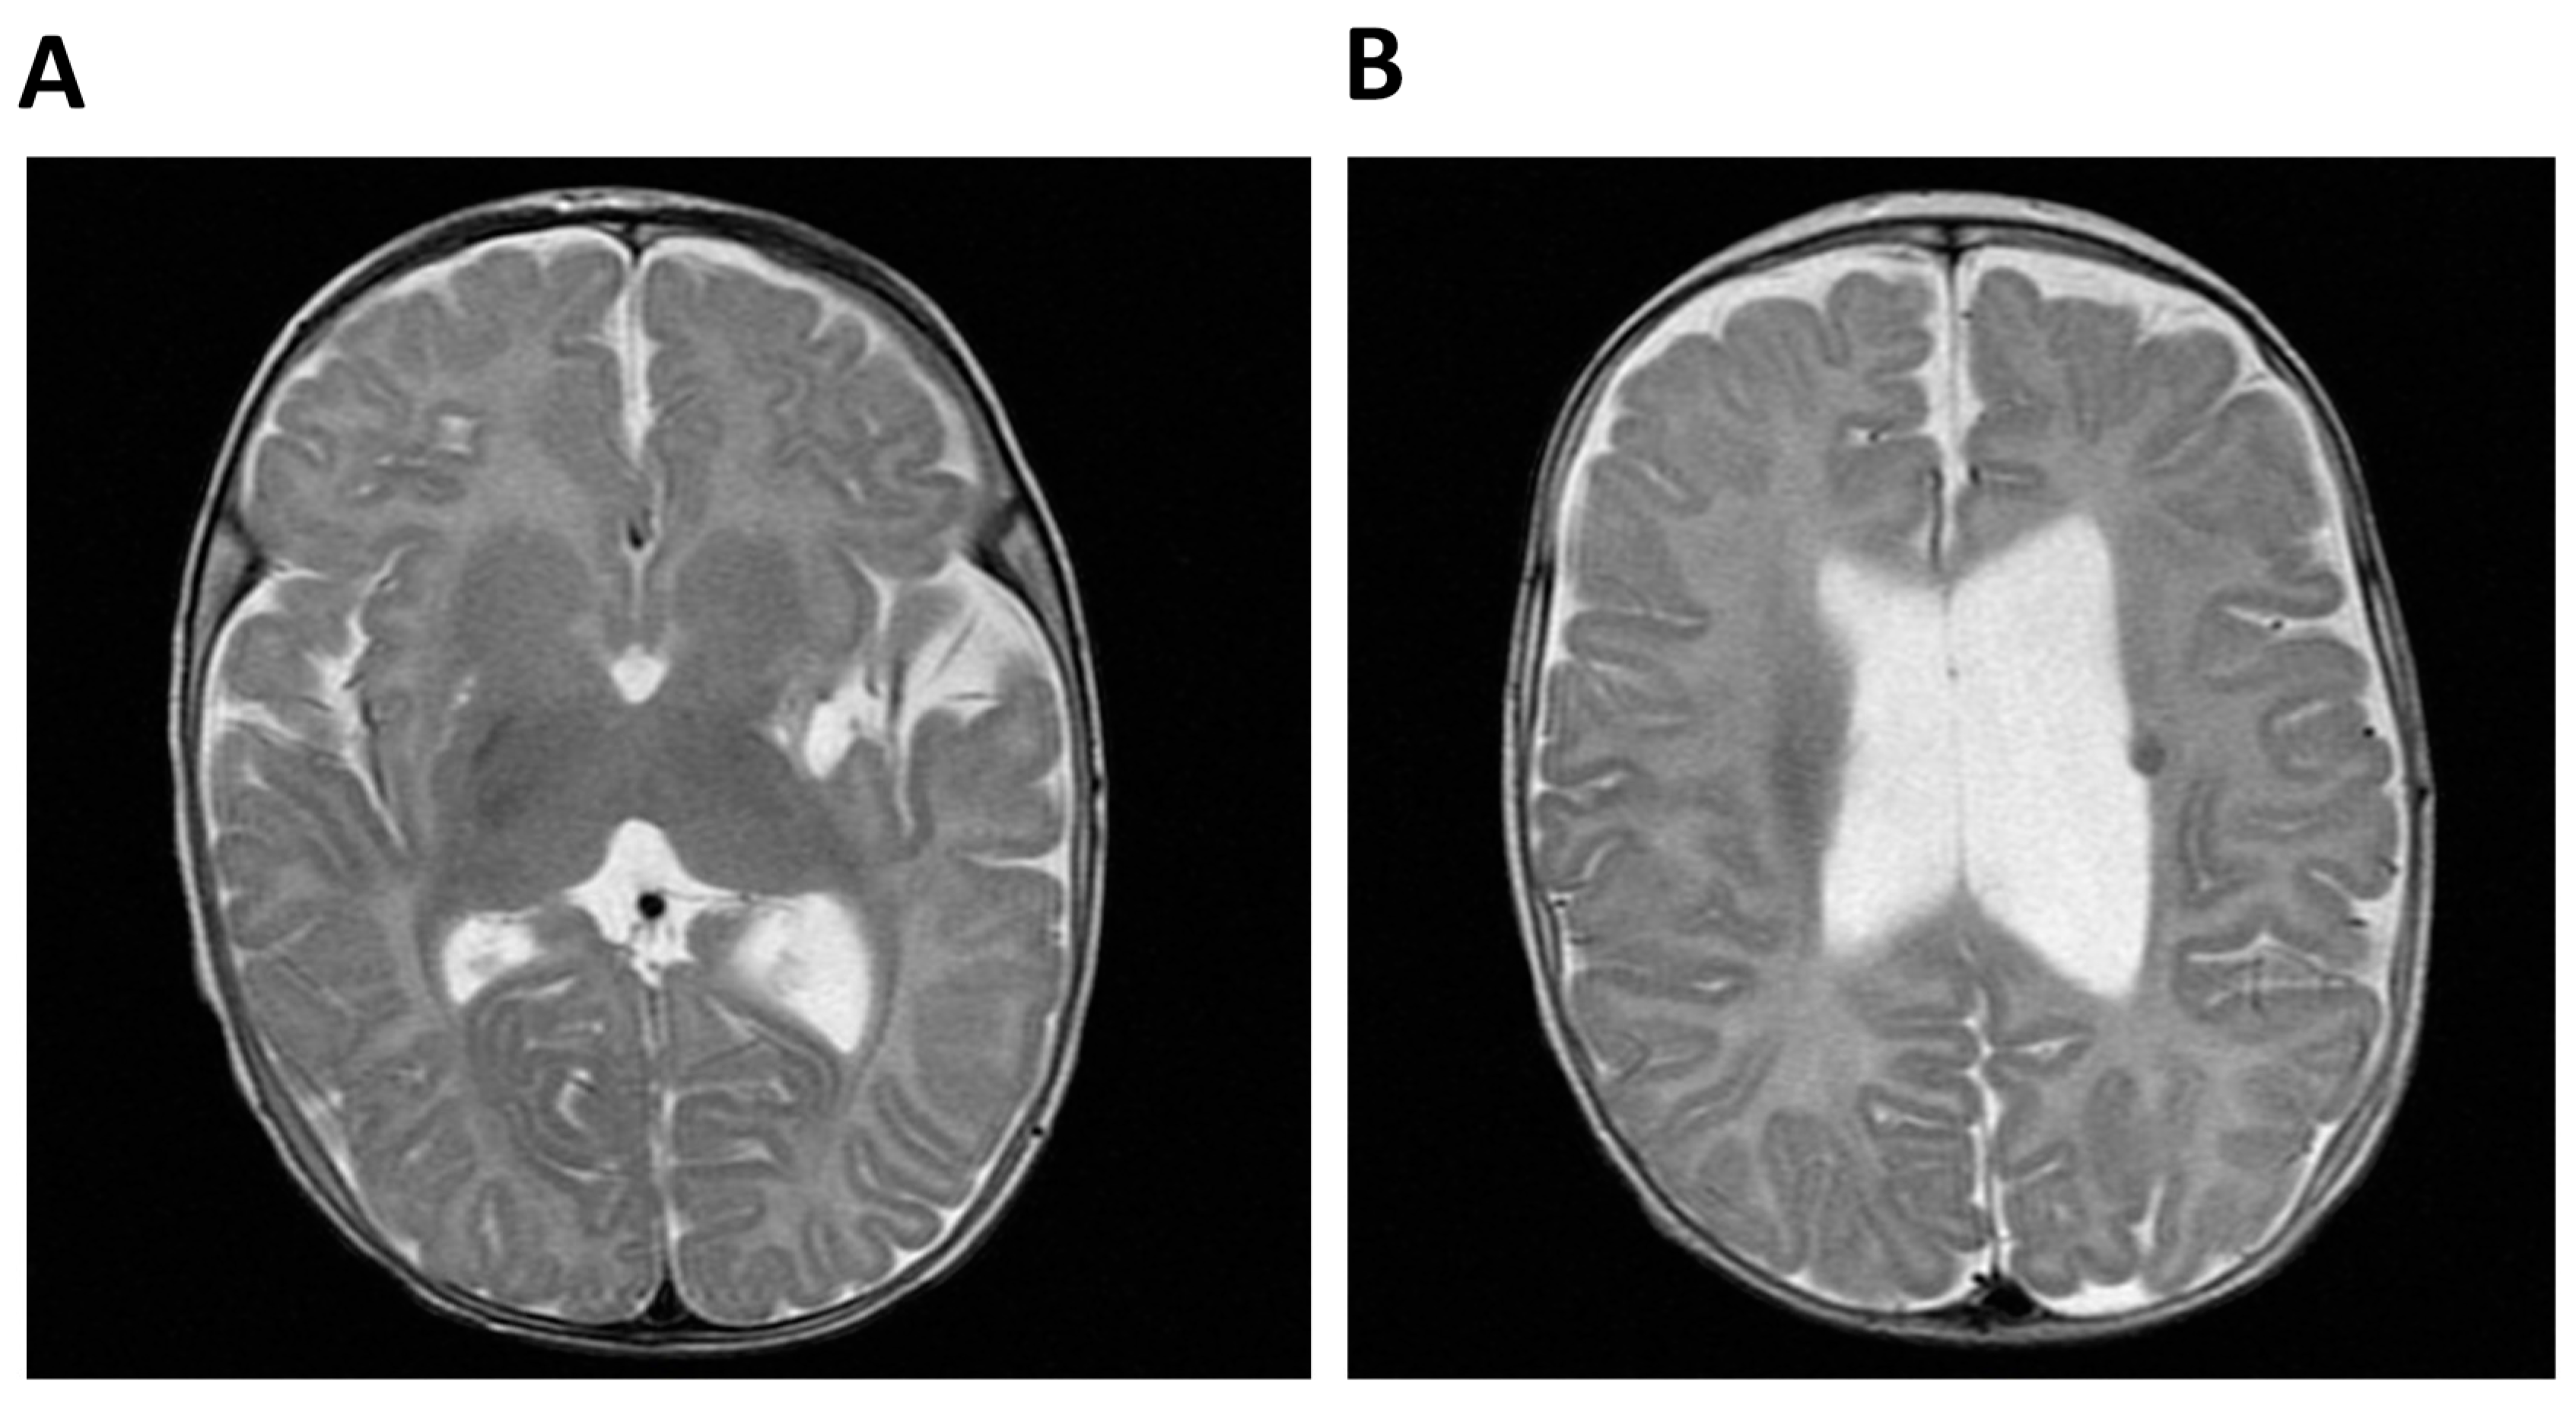

| Cerebral anomalies | Ventriculomegaly | + | − | NR | NR | NR |

| Hypoplasia corpus callosum | + | − | NR | NR | NR | |

| Strokes | + | − | NR | NR | − | |